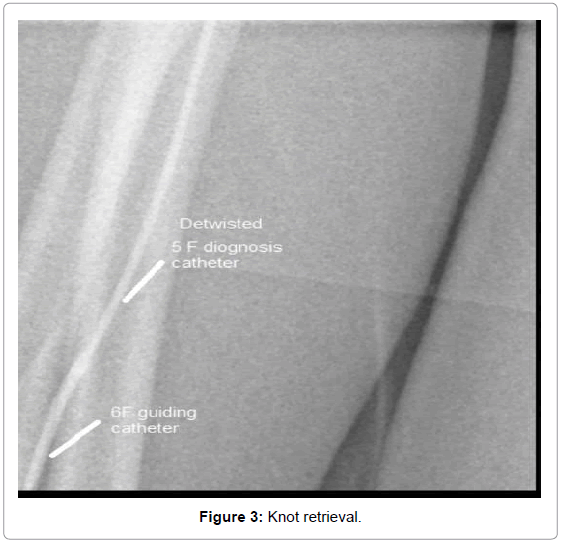

Radial Retrieval of Twisted Diagnosis Catheter Using Mother in Child Technique